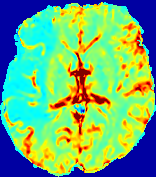

4.3.2 Diffusion Imaging via Advection-Diffusion

Slice #1Slice #2Slice #3Slice #4Slice #5Slice #6Dgtsuperscript𝐷gtD^{\text{gt}}Refer to captionRefer to captionRefer to captionRefer to captionRefer to captionRefer to captionDestsuperscript𝐷estD^{\text{est}}Refer to captionRefer to captionRefer to captionRefer to captionRefer to captionRefer to captionRefer to caption0.300.300.300.240.240.240.180.180.180.120.120.120.060.060.060.000.000.00(mm2/s)𝑚superscript𝑚2𝑠(mm^{2}/s)𝐕est𝟐subscriptnormsuperscript𝐕est2\|\bf{V}^{\text{est}}\|_{2}Refer to captionRefer to captionRefer to captionRefer to captionRefer to captionRefer to captionRefer to caption0.00300.00300.00300.00240.00240.00240.00180.00180.00180.00120.00120.00120.00060.00060.00060.00000.00000.0000(mm/s)𝑚𝑚𝑠(mm/s)

Figure 15: PIANO identifiability testing: diffusion imaging via advection-diffusion. Top row shows Dgtsuperscript𝐷gtD^{\text{gt}} used for simulating ground truth pure diffusion. Rows below show the estimated Destsuperscript𝐷estD^{\text{est}} and 𝐕est2subscriptnormsuperscript𝐕est2\|{\bf{V}}^{\text{est}}\|_{2} on corresponding slices. Note that the plotted value scale for 𝐕est2subscriptnormsuperscript𝐕est2\|{\bf{V}}^{\text{est}}\|_{2} is 0.01 of that for Dgtsuperscript𝐷gtD^{\text{gt}} and Destsuperscript𝐷estD^{\text{est}}.

Similarly, we test the behavior of PIANO when estimating both advection and diffusion from a pure diffusion-driven process. The goal is to determine if PIANO is able to recognize that there is only diffusion governing the given concentration time-series. We use the same ‘Diffusion Imaging’ data simulation of Sec. 4.2.1 as the concentration dataset, PIANO estimates both velocity 𝐕estsuperscript𝐕est{\bf{V}}^{\text{est}} and diffusivity Destsuperscript𝐷estD^{\text{est}}. Estimation results in Fig. 15 confirm PIANO’s identifiability again: the estimated 𝐕est2subscriptnormsuperscript𝐕est2\|{\bf{V}}^{\text{est}}\|_{2} is almost invisible compared to Destsuperscript𝐷estD^{\text{est}}, even plotted with a 1%percent11\% value range compared to that for Destsuperscript𝐷estD^{\text{est}}. On the other hand, Destsuperscript𝐷estD^{\text{est}} achieves comparable estimation performance as ‘Diffusion Imaging via Diffusion’ in which PIANO predicts Destsuperscript𝐷estD^{\text{est}} alone (shown in Fig. 13).